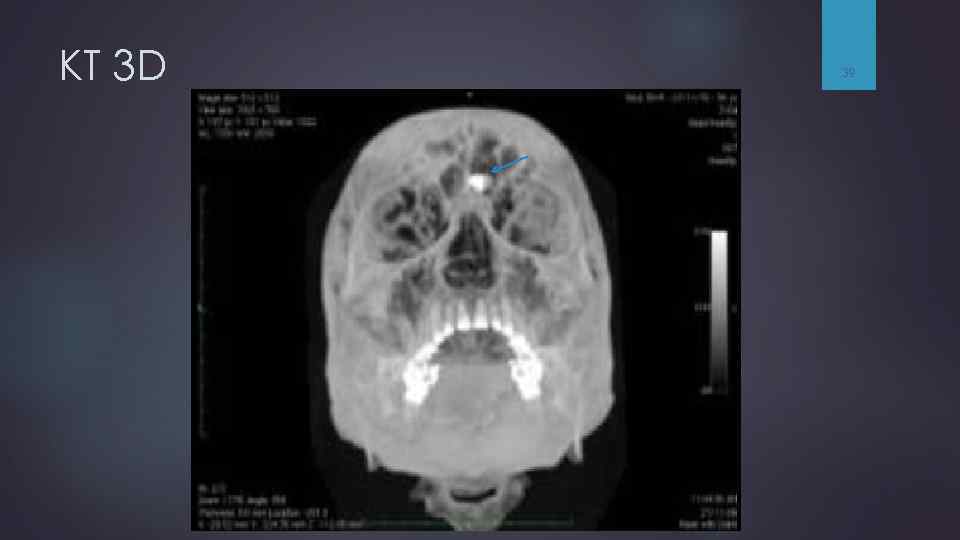

КТ 3 D 39